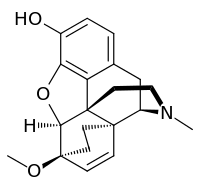

In the 19th century, two major scientific advances were made that had far-reaching effects. Around 1804, German pharmacist Friedrich Sertürner isolated morphine from opium. He described its crystallization, structure, and pharmacological properties in a well-received paper in 1817.[211][213][208][214] Morphine was the first alkaloid to be isolated from any medicinal plant, the beginning of modern scientific drug discovery.[211][215]

Several semi-synthetic opioids were developed in Germany in the 1910s. The first, oxymorphone, was synthesized from thebaine, an opioid alkaloid in opium poppies, in 1914.[228] Next, Martin Freund and Edmund Speyer developed oxycodone, also from thebaine, at the University of Frankfurt in 1916.[229] In 1920, hydrocodone was prepared by Carl Mannich and Helene Löwenheim, deriving it from codeine. In 1924, hydromorphone was synthesized by adding hydrogen to morphine. Etorphine was synthesized in 1960, from the oripavine in opium poppy straw. Buprenorphine was discovered in 1972.[228]

Opium alkaloids and derivatives

Phenanthrenes naturally occurring in (opium):